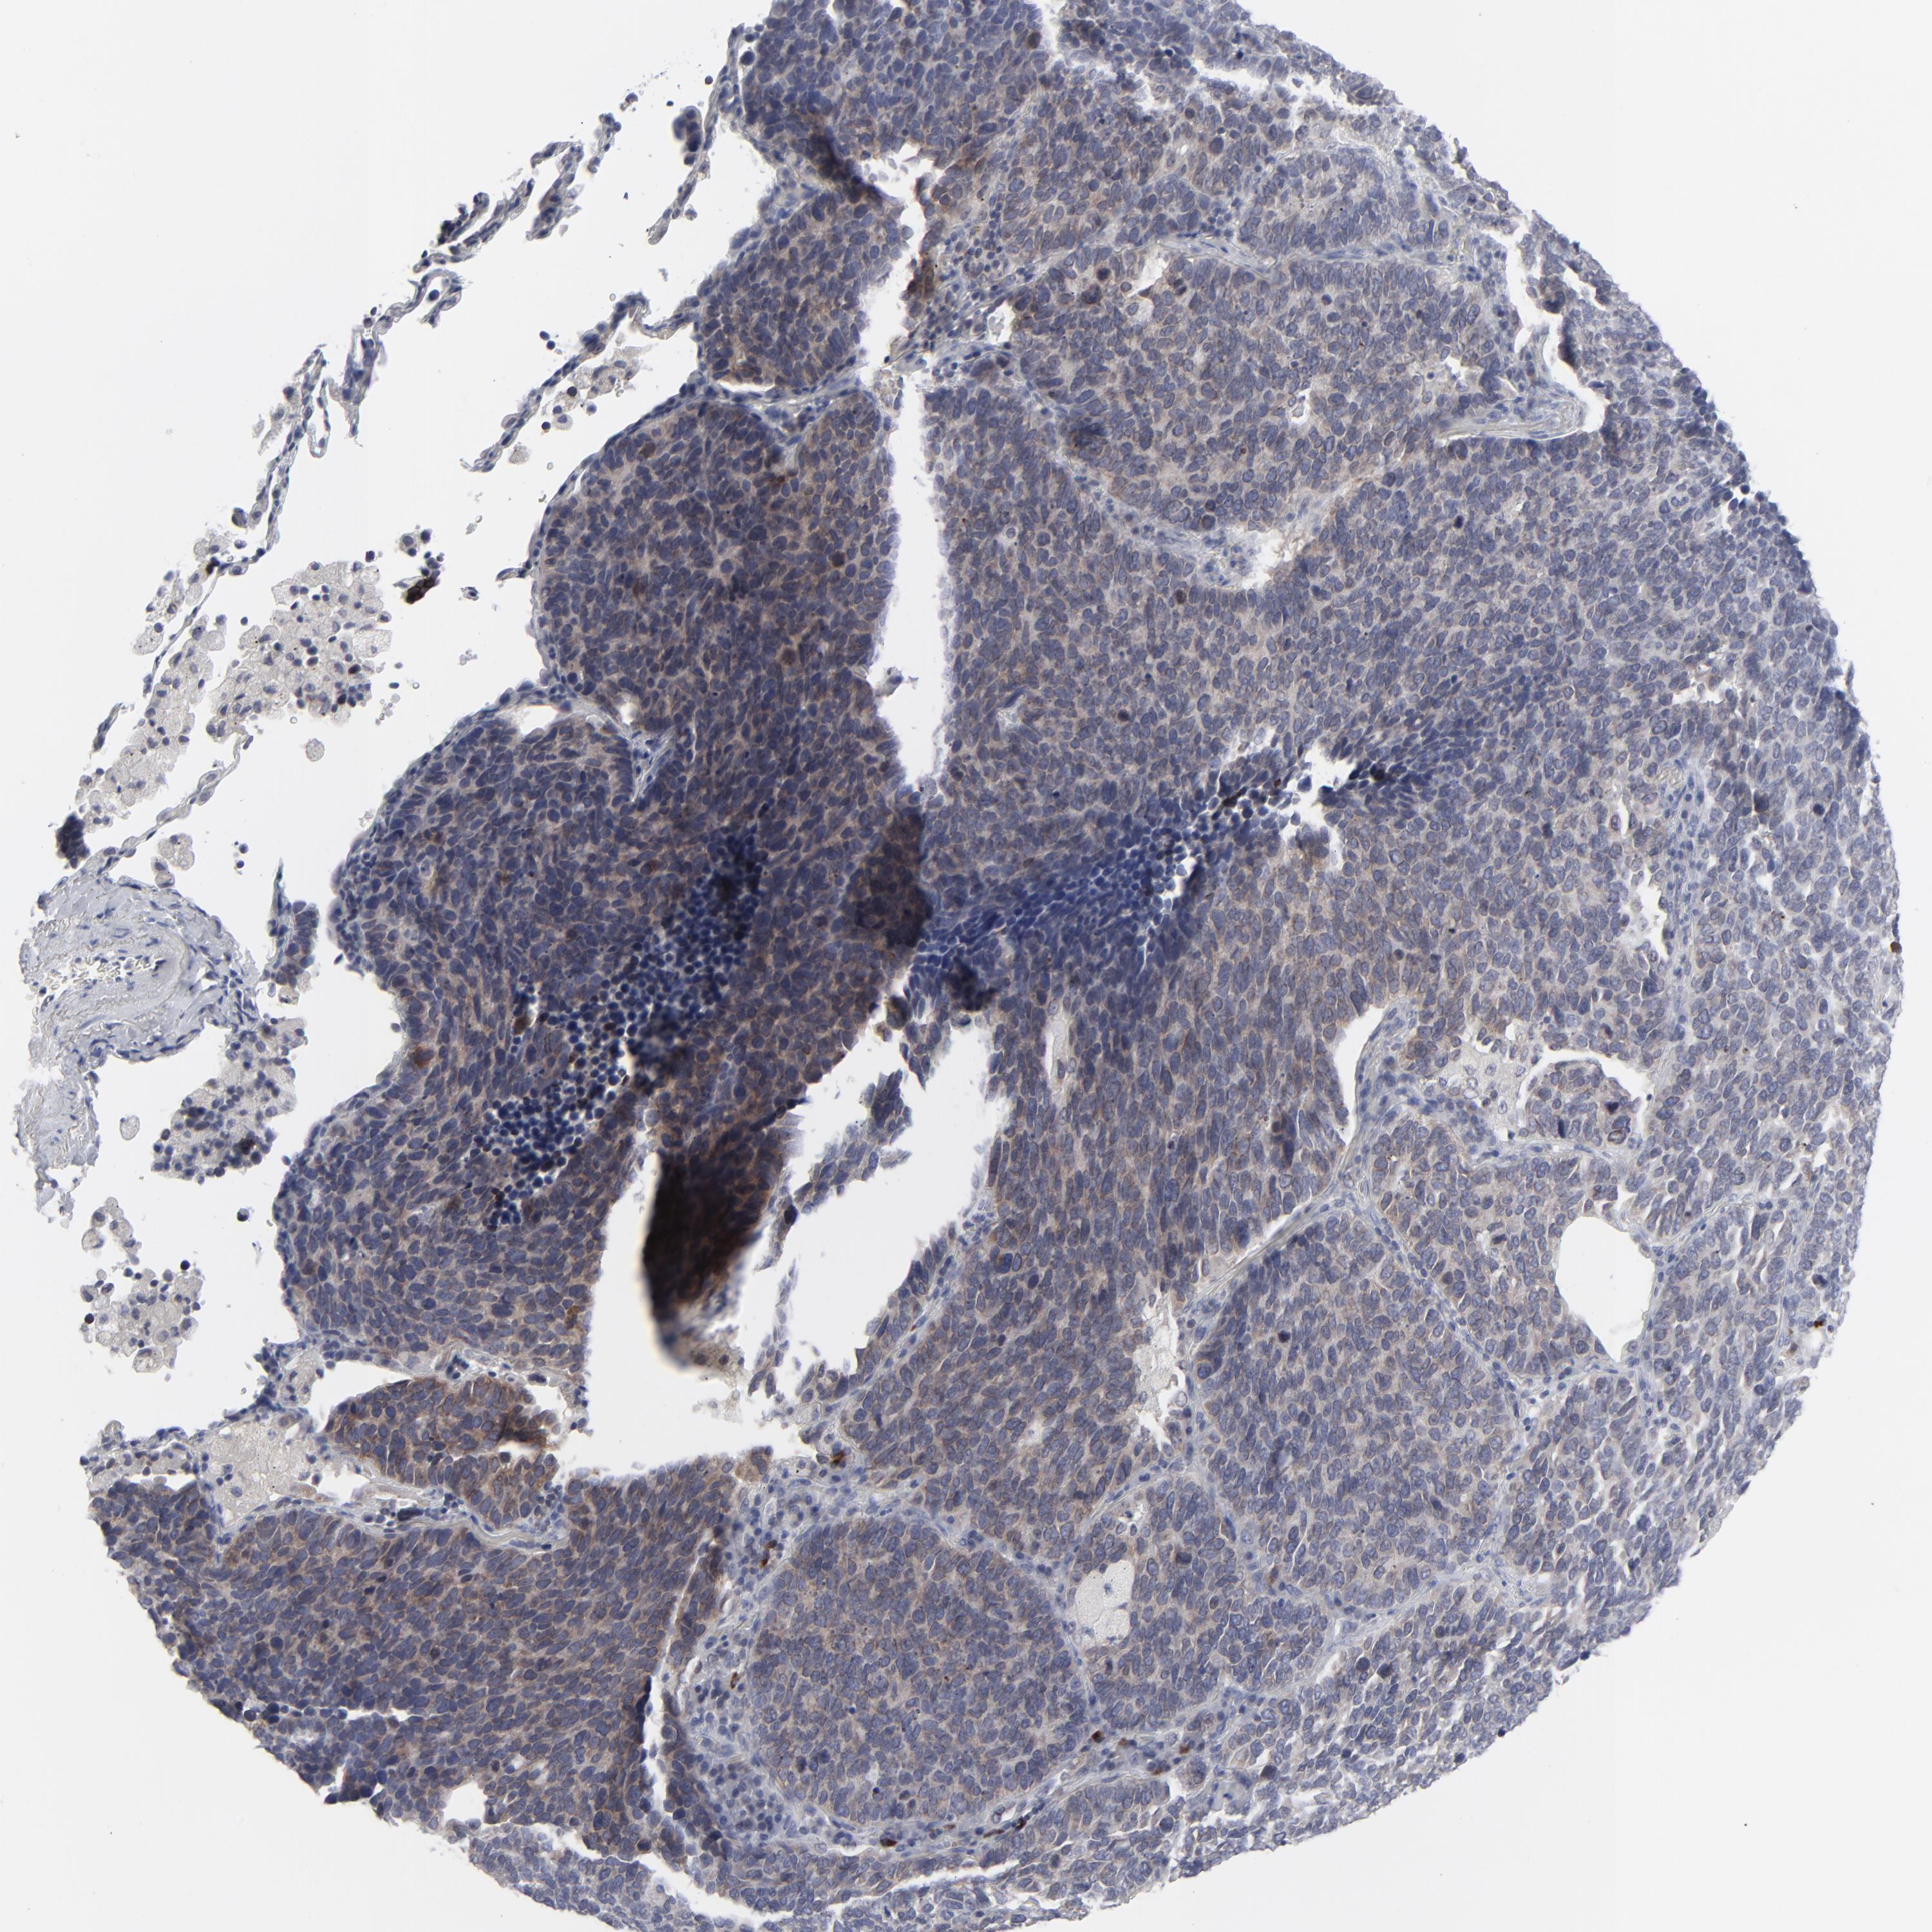

CANCER LUNG CANCER Show tissue menu